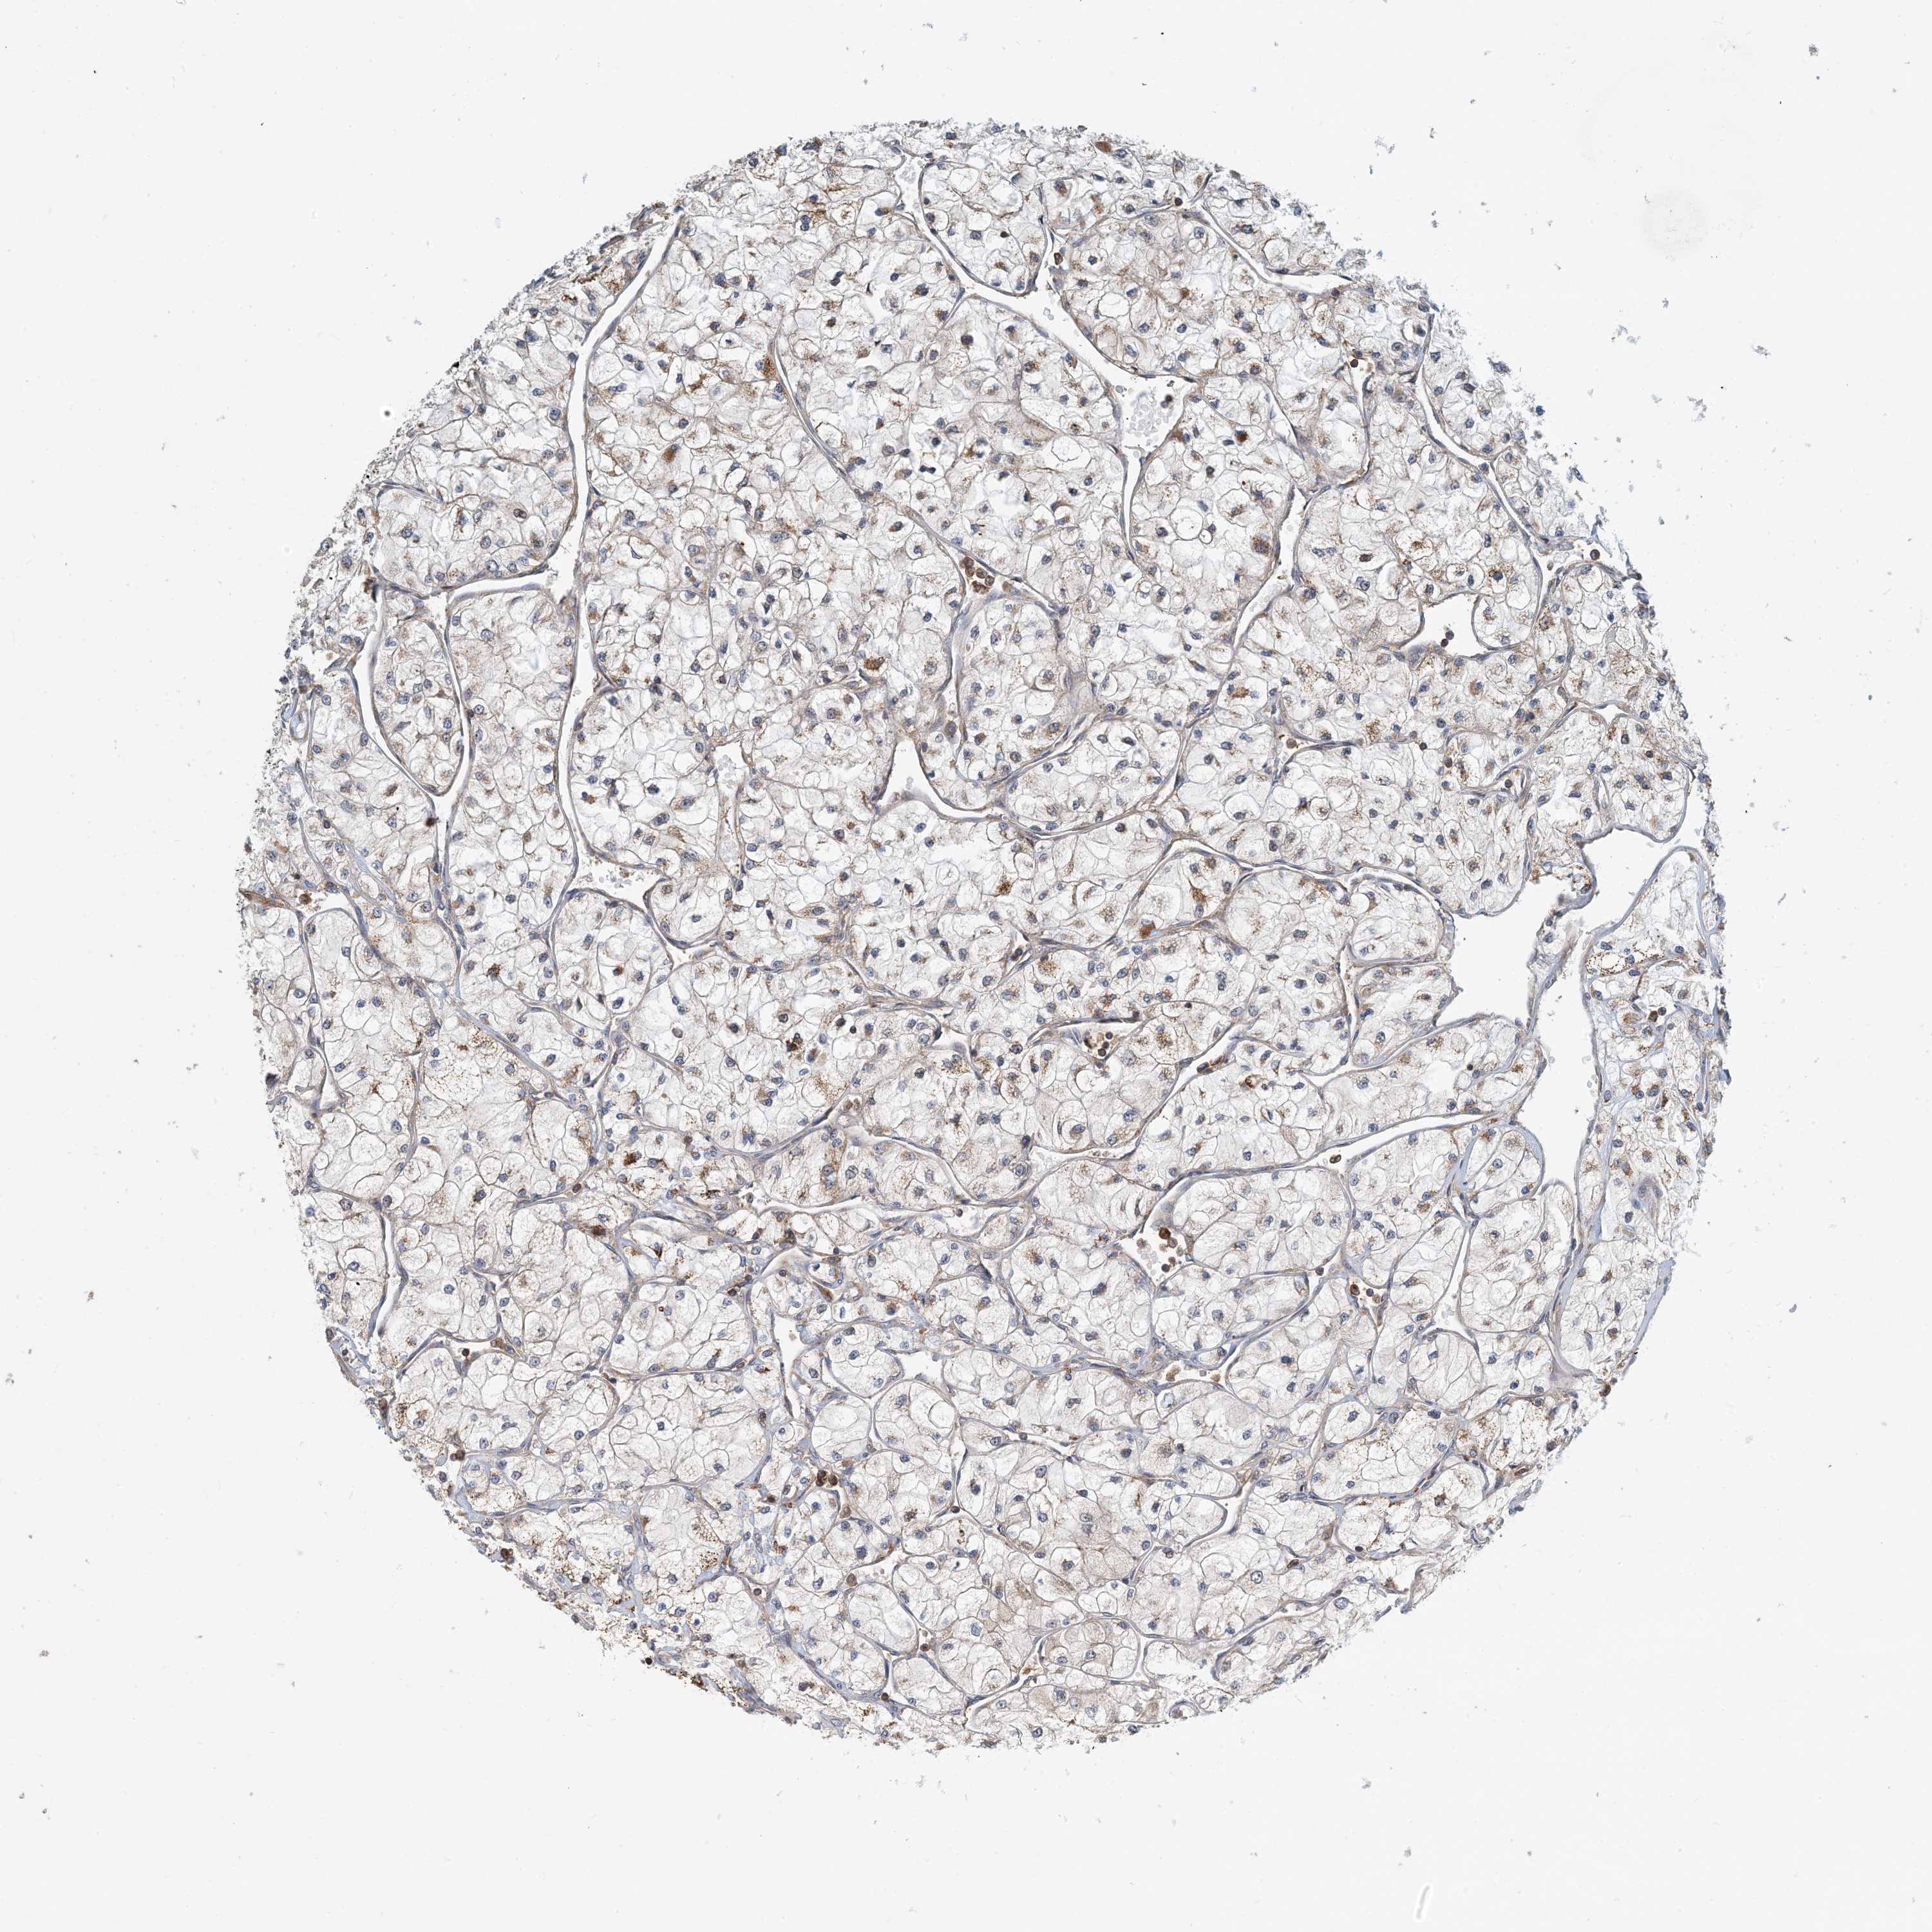

Average pTPM 8.9

Number of samples 100